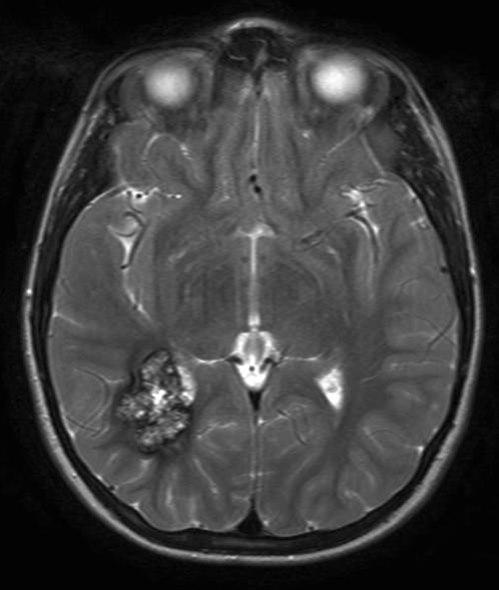

Kavernøst hemangiom, aksialt snitt 2

kavernøst hemangiom 2

Gjengitt med tillatelse av Radiologisk avdeling, Universitetssykehuset Nord-Norge